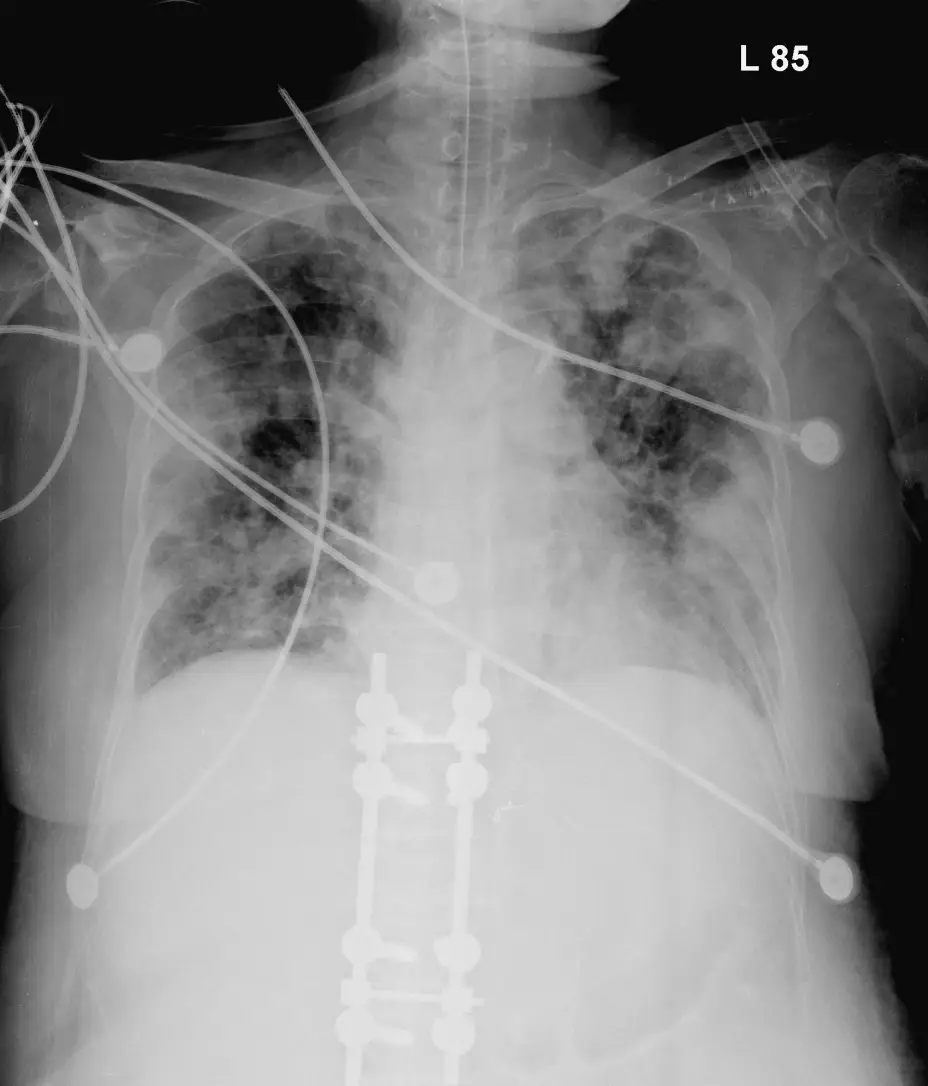

病患胸部X光片與電腦斷層影像如圖, 以下診斷何者最為可能:

從胸部X光片可見:

- 雙側多發性邊緣模糊的結節狀及塌陷狀浸潤影,主要集中於下肺場,呈不規則分布;

- 部分病灶已出現空洞化(中央透亮區域);

- 伴有少量胸腔積液及醫療器械(中央導管、體外支架等)提示病人重症且可能有導管相關感染風險。

上述影像特徵符合「多發周邊結節、楔形浸潤、快速空洞化、feeding vessel sign」的典型 septic pulmonary emboli 圖像學表現。